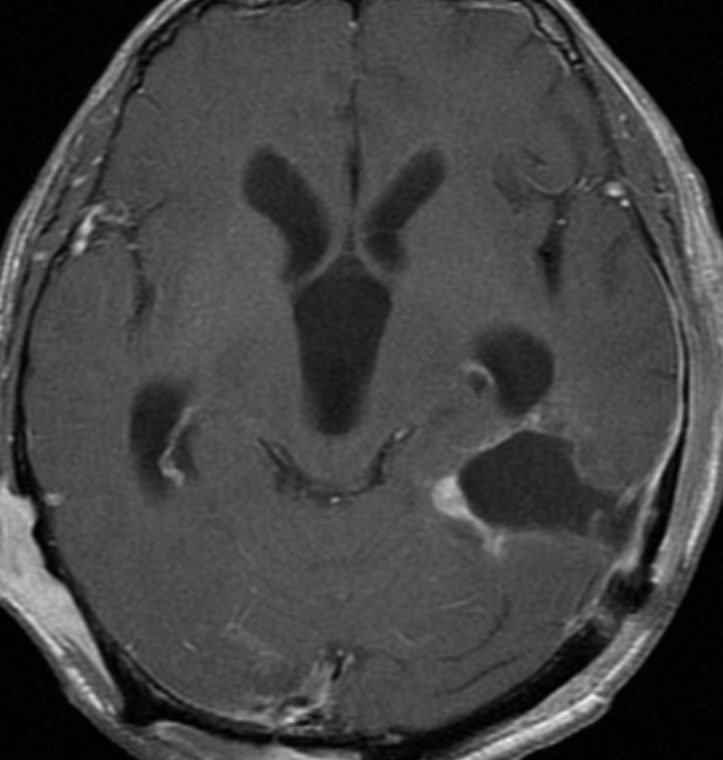

もともと停止性水頭症があり経過観察を受けていたNF-1の患者さんに発生したものです。嘔気と左片麻痺で発症しました。 開頭手術で亜全摘出(ほぼ全摘)しました。

術後に小さな腫瘍が残っていた(左の画像)ので54Gy/27frの放射線治療をしましたが,無効でした。結局,再開頭手術で残存腫瘍を摘出しました。3年後に同じ部位で再発(中央の画像)したので,また開頭手術で摘出しました。そのまた3年後に同じ部位で再発しました(右側の画像)。この様に,摘出しきれなければ治らないし,摘出できれば治る可能性の高い腫瘍です。腫瘍床での再発は多いものの,転移とか脳深部への浸潤性増殖は少ないといえる腫瘍です。放射線治療が効きにくいということを併せて,atypical meningioma WHO grade 2と似た性格を有しています。